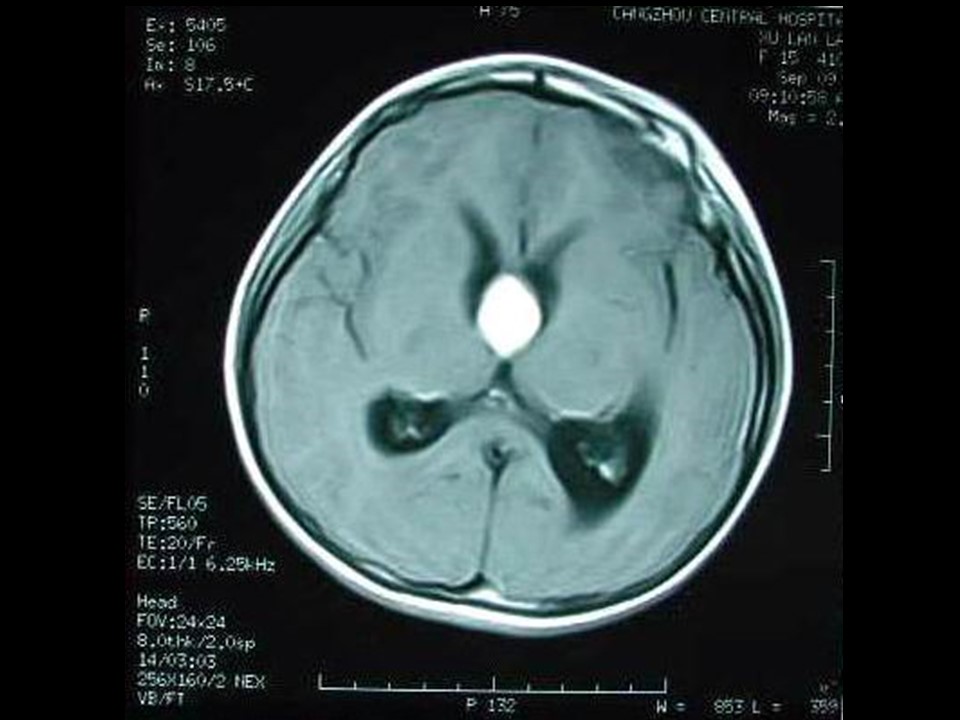

“垂体瘤的影像诊断” 的相关文章